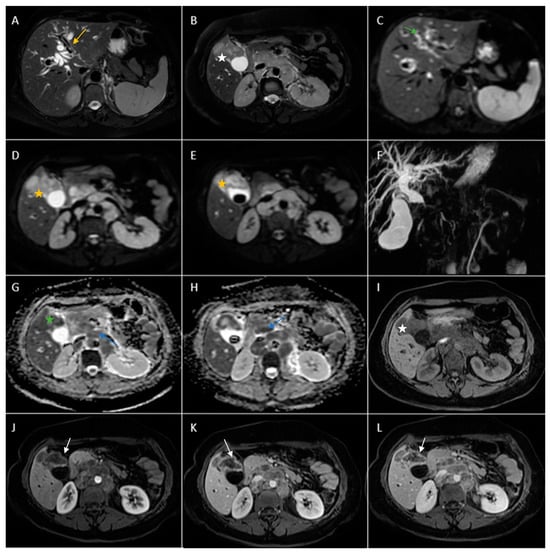

Figure 5. Abdominal MRI vividly illustrating synchronous gallbladder and biliary tract carcinoma with multiple large lymphadenopathies localized in the hepatic hilum, surrounding the cephalic region of the pancreas and in the celiac region. (A) Axial T2-weighted FS showed significant intrahepatic biliary dilatation in both hepatic lobes (yellow arrow). (B) Axial T2-weighted FS showed hypointense intraluminal gallbladder mass (white star) and multiple large lymphadenopathies. (C) Axial diffusion-weighted imaging (DWI B800) showed irregular, asymmetrical thickening of the walls of the intrahepatic bile ducts with high signal intensity suggestive of cholangitis (green arrow). (D,E). DWI B800 highlighted the gallbladder mass; inhomogeneous areas of high signal (yellow stars). (F) Coronal 3D MRCP showed enlarged gallbladder with an intraluminal gallstone and dilated intrahepatic and extrahepatic biliary tree. (G,H). On apparent diffusion coefficient (ADC) map, the gallbladder mass is dark, illustrating markedly diffusion restriction (green star). Multiple large lymphadenopathies are also observed mainly in the lombo-aortic region, in the cephalic pancreatic region and in the hepatic hilum (blue arrow). (I) Axial T1-weighted image showing hypointense irregular tumoral gallbladder mass (white star). (JL). Axial contrast-enhanced (arterial phase followed by venous phase) T1-weighted image showing rim-enhancing of the tumoral gallbladder mass (white arrow).

Contrast-enhanced emergency CT was performed (Figure 4), which richly highlighted a large heterogeneous intraluminal gallbladder mass, localized in the gallbladder fundus, measuring 58/34 mm, irregular, peripheral contrast enhancement on arterial and venous phase and with central hypodensity suggestive of areas of necrosis, extending to the surrounding liver (segment V) (Panel A and Panel C). CT showed a gallstone (17 mm) wedged in the gallbladder neck and intrahepatic biliary dilatation (Panel C and D). The common bile duct was dilated due to the presence of a possible tumoral extension to biliary tract or by the compressive effect of the multiple hilar lymphadenopathies; mesenteric, celiac and retroperitoneal lymphadenopathies with areas of necrosis, measuring up to 25/15 mm were also noted (Panel B). Abdominal contrast-enhanced MRI was performed (Figure 5).